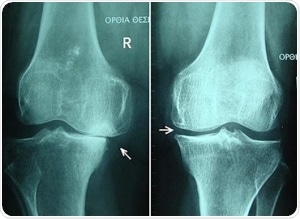

Knee osteoarthritis stages II and III by Harrygouvas at Greek Wikipedia. [CC BY-SA 3.0 or GFDL 1.3], from Wikimedia Commons

Osteoarthritis is a common degenerative condition. It is characterized by the diminution of cartilage in and around the joints which results in pain and loss of mobility. Age is seen to be the most common cause of osteoarthritis, but, traumatic joint injury can also cause joint degeneration in people of all ages. The progression of the condition can be slowed and symptoms can certainly be managed, however the underlying causes that lead to the development of this condition cannot be reversed.

The current standards giving recommendations on the diagnosis and treatment of osteoarthritis depend on radiographic imaging to detect either of two things. First, the hardening of the subchondral layer, or second, a reduction in joint space and visual and tactile inspection during arthroscopic surgery.